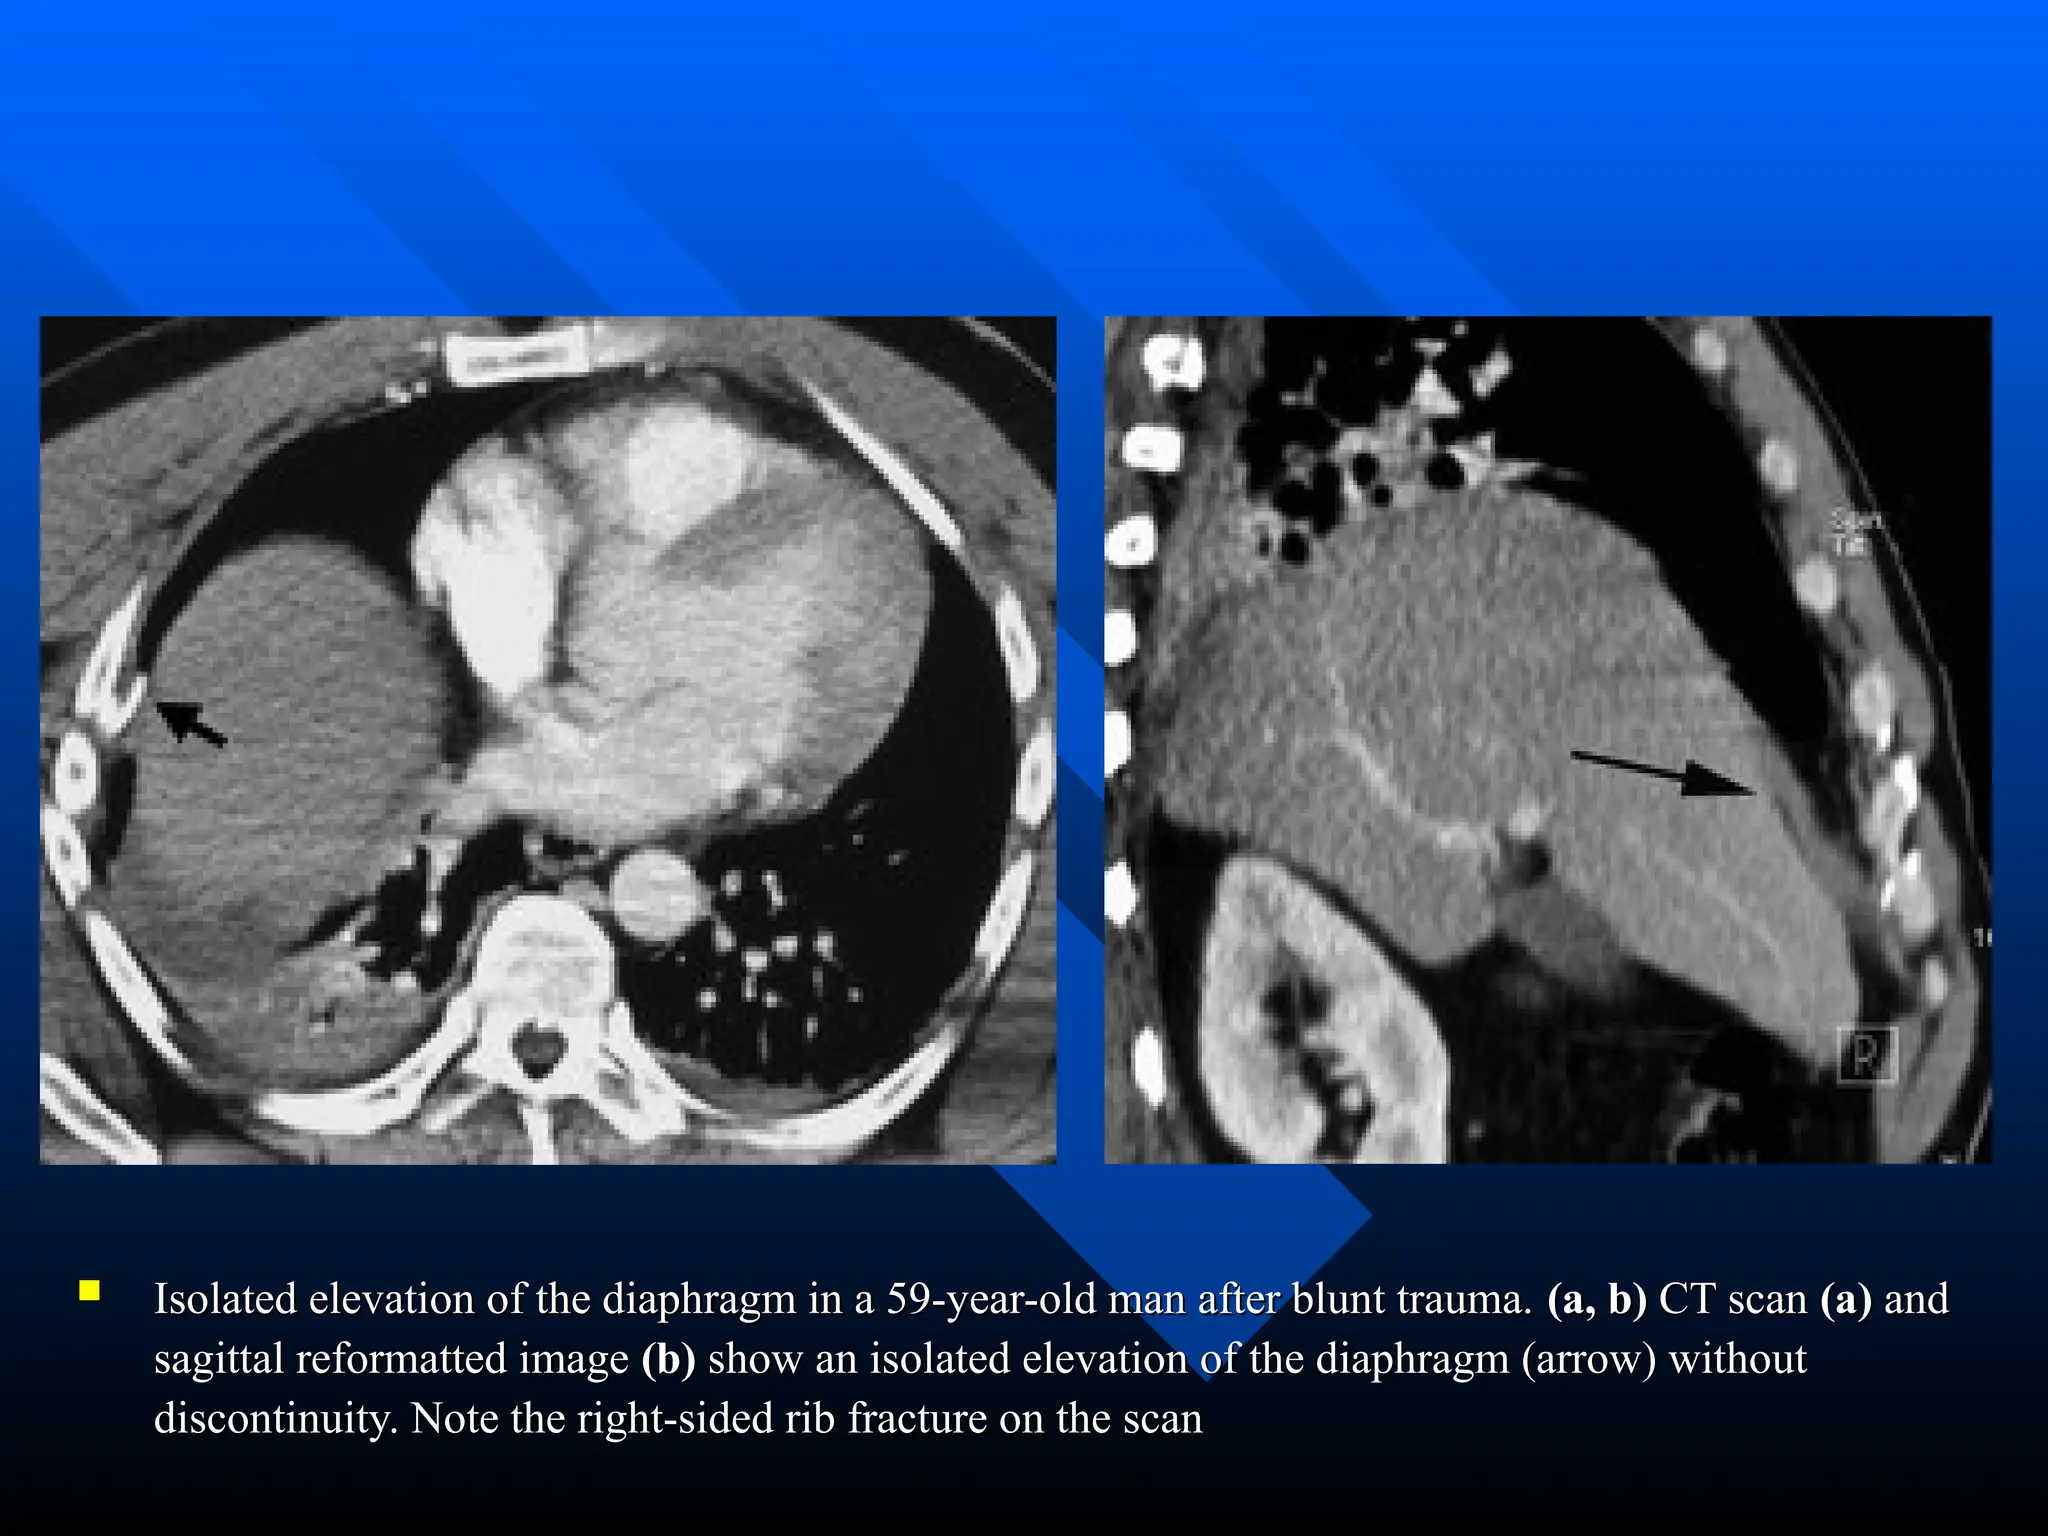

 Isolated elevation of the diaphragm in a 59-year-old man after blunt trauma.

Isolated elevation of the diaphragm in a 59-year-old man after blunt trauma. (a, b)

(a, b) CT scan

CT scan (a)

(a) and

and

sagittal reformatted image

sagittal reformatted image (b)

(b) show an isolated elevation of the diaphragm (arrow) without

show an isolated elevation of the diaphragm (arrow) without

discontinuity. Note the right-sided rib fracture on the scan